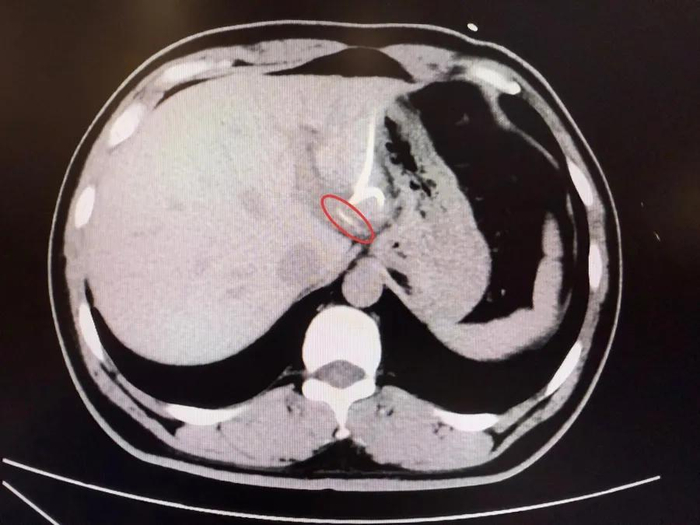

Mãi đến khi chụp CT, các bác sĩ mới phát hiện một vật thể dài, nhọn trong gan trái, gần vùng nối với dạ dày, hình dạng giống hệt… một chiếc xương cá! Hóa ra, chiếc xương này đã xuyên qua thành dạ dày, “chui” thẳng vào gan, gây nhiễm trùng và tạo ổ mủ lớn.

Sau hơn 3 tiếng đồng hồ, các bác sĩ đã tìm thấy chiếc xương cá dài 3,5cm, sắc nhọn như kim, cắm sâu trong gan trái. Sau ca mổ, anh Lý hồi phục tốt, nhiệt độ cơ thể trở lại bình thường, ổ áp xe dần tiêu biến và quan trọng hơn cả, anh giữ được nguyên vẹn lá gan của mình .